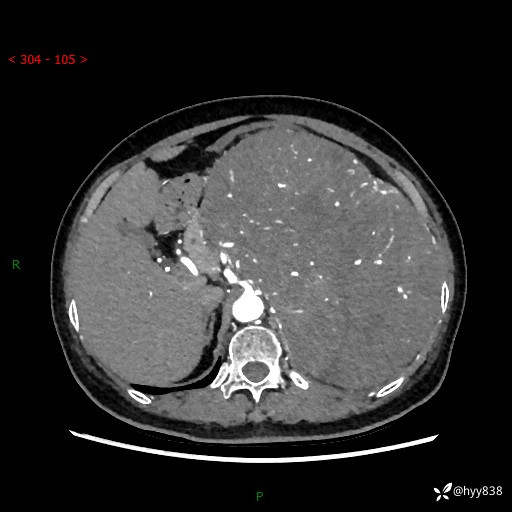

据说只有腹膜后,才能见到如此巨大的肿块---(有结果)

主诉:发现腹膜后占位1周

简要病史:患者1周前因头晕在当地第二人民医院检查发现左侧腹膜后区巨大富血供占位性病变,患者自诉腹部稍硬,无其他不适,无血尿,无腰痛等不适,患者为求进一步治疗来我院,门诊以“腹膜后占位性病变”收入我科。 起病以来,患者精神、饮食、睡眠可,大便正常,小便如上述,体力体重无明显改变。

临床诊断:腹膜后占位

腹部CT增强(动脉期+静脉期 ) ---平扫外院